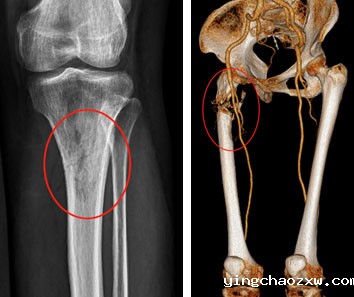

县总医院骨科团队综合研判患者病情,及时制定合理、安全、有效的治疗方案,决定为患者行右侧股骨骨肿瘤切除,肿瘤型人工髋关节置换术。因患者右股骨髓腔细小,常规人工髋关节体假体无法使用,需使用特殊假体,根据患者DR、CT,向生产厂家为患者量身定做了个性化定制型人工肿瘤髋关节假体,征对患者髓腔细,假体特别设计了个性化结合部加强套筒,确保假体强度及使用安全,术前行右下肢动脉CTA,严格评估右股骨肿瘤营养动脉血供情况,避免术中出现难以控制出血,经精心准备,在主任医师陈志强院长带领下,总医院骨科近日成功为患者实施了右侧股骨近端恶性肿瘤骨转移切除、定制肿瘤型人工髋关节置换术。手术历时2小时完成,术中患者病情平稳,术后患者疼痛疼痛消除,右下肢活动明显改善,患者的生活质量得到了极大提高,家属也十分满意。